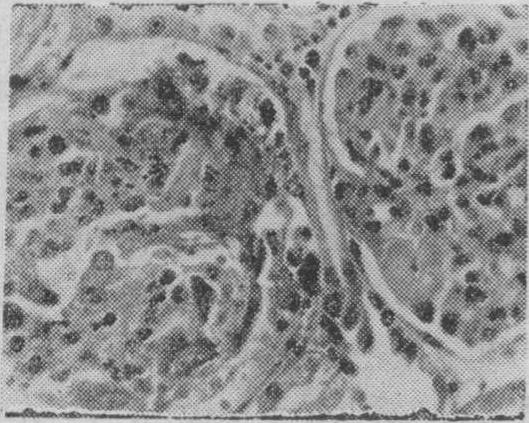

病肾的急性期病变主要为增殖性肾炎,伴有蛋白质渗出(图1)。数周后肾小球内新月体形成(图2),逐渐发展为整个小球纤维化及玻璃样变(图3)。电镜检查肾小球基膜增厚、破裂,沿肾小球基膜内皮细胞下有电子致密物沉积(图4)。免疫荧光检查肾小球及部分肾小管基膜上有免疫球蛋白(在第一阶段只有异体的,第二阶段又加上自体的)及补体,有时还有纤维蛋白原呈均匀的线条状沉积。

图2肾小球毛细血管壁变性坏死,大量纤维素渗出,沉积于肾小囊 (H.E.×500)